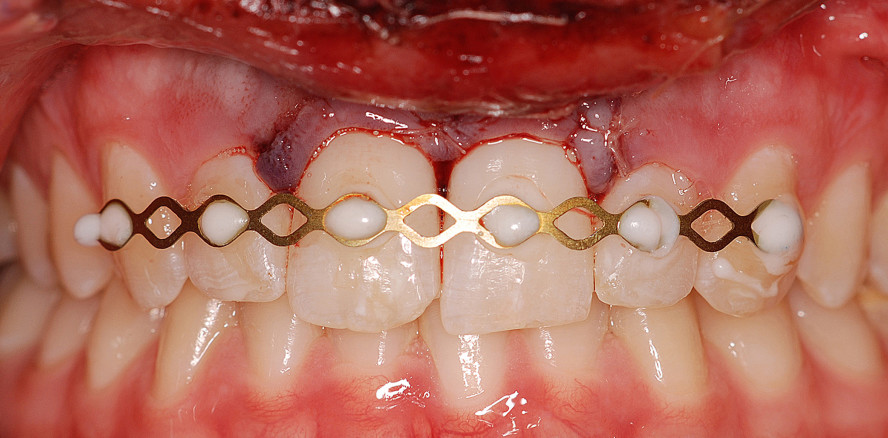

Im Rahmen der Ersttherapie wurden die Zähne 11 und 21 in der Unfallnacht replantiert und mithilfe eines Titanium Trauma Splints (Medartis AG, Schweiz) geschient (Abb. 1b). Die Zähne lagen circa zwei Stunden am Unfallort und wurden vor der Replantation für 30 Minuten in einer physiologischen Nährlösung (Dentosafe) zwischengelagert. Nach Spülung mit physiologischer Kochsalzlösung und klinischer bzw. röntgenologischer Inspektion der leeren Alveolen (Abb. 2a) wurden die Zähne langsam sowie drucklos replantiert und die korrekte Positionierung röntgenologisch überprüft (Abb. 2b).